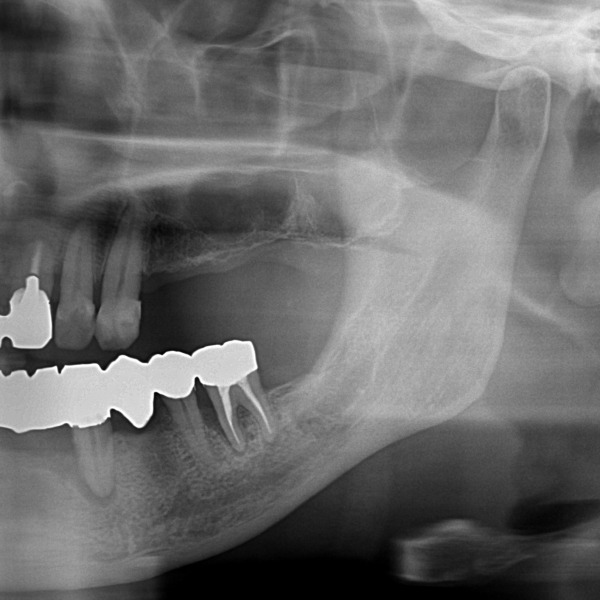

こちらが抜歯後、3ヶ月のレントゲン写真になります。